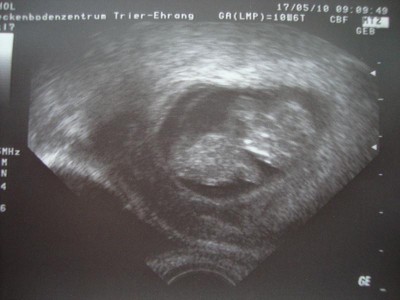

ja jetzt ist wieder alles ok. Nachdem ich starke Blutungen hatte musste ich erst 10 Tage zu Hause liegen und als dann nochmal heftige Blutug kam nochmal 10 im Krankenhaus! :roll:

Es war ein riesiges Hämatom und die Gefahr war ziemlich groß dass entweder das Baby mit abblutet oder die Versorgung abgedrückt würde, weils direkt an der FH war, aber Hanni hat es zum Glück gut überstaden, wächst und gedeiht prächtig. Hoffe es bleibt jetzt so und ich kann einfach ganz normal schwanger sein. Nächsten Mittwoch hab ich wieder Termin bei meinem FA. Ich häng noch das neueste US-Foto an.

US Bild 20.05.2010 004kl.jpg